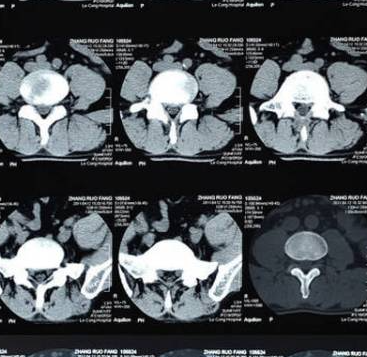

如果大家发现自己患有腰间盘突出,最好先到医院进行CT检查,了解清楚患病的情况,然后对症治疗。让自己在科学治疗的帮助下摆脱伤害,恢复健康。